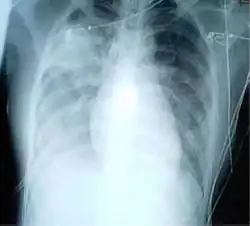

A chest radiograph is frequently used in diagnosis.[23] In people with mild disease, imaging is needed only in those with potential complications, those not having improved with treatment, or those in which the cause is uncertain.[23][69] If a person is sufficiently sick to require hospitalization, a chest radiograph is recommended.[69] Findings do not always match the severity of disease and do not reliably separate between bacterial and viral infection.[23]

X-ray presentations of pneumonia may be classified as lobar pneumonia, bronchopneumonia, lobular pneumonia, and interstitial pneumonia.[75] Bacterial, community-acquired pneumonia classically show lung consolidation of one lung segmental lobe, which is known as lobar pneumonia.[42] However, findings may vary, and other patterns are common in other types of pneumonia.[42] Aspiration pneumonia may present with bilateral opacities primarily in the bases of the lungs and on the right side.[42] Radiographs of viral pneumonia may appear normal, appear hyper-inflated, have bilateral patchy areas, or present similar to bacterial pneumonia with lobar consolidation.[42] Radiologic findings may not be present in the early stages of the disease, especially in the presence of dehydration, or may be difficult to interpret in the obese or those with a history of lung disease.[24] Complications such as pleural effusion may also be found on chest radiographs. Laterolateral chest radiographs can increase the diagnostic accuracy of lung consolidation and pleural effusion.[41]